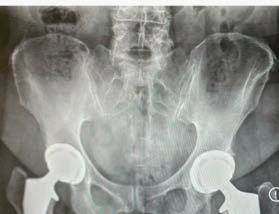

PAIN-RELIEVING DOUBLE HIP REPLACEMENT

SURGERY HELPS A WOMAN REGAIN HER ACTIVE LIFE.

Cheryl Allen-Munley of Tewksbury never imagined she’d need a hip replacement, let alone two. Until 2022, the now-68year-old retired engineer, who teaches math at a local college, had been vibrant and active—an avid horse rider who also loved to dance, walk, bike and do Zumba workouts.

Stephen Kayiaros, MD, Medical Director of the Joint Surgery Program at Robert Wood Johnson University Hospital Somerset, uses the anterior approach—a tissue-sparing technique that can lead to less pain, faster recovery and improved mobility—for more than 99 percent of his hip replacements.

He could plainly see the cause of Cheryl’s pain. “X-rays showed degeneration in her hips that was very advanced,” he says. “She had no cartilage

left. It was bone-on-bone.”

A diagnosis of advanced osteoarthritis from ongoing wear and tear sometimes shocks people, Dr. Kayiaros says, especially when symptoms seem to develop quickly. “But arthritis doesn’t happen overnight,” he says. “It can go undetected for years. Then some event triggers an avalanche of symptoms. People may think the event caused the arthritis, but that’s rarely the case.”

Cheryl’s anatomy suggested she also may have been born with subtle hip dysplasia—a misalignment in the joint that can predispose people to arthritis later in life.

“I was now in terrible pain in both hips,” Cheryl says. She and Dr. Kayiaros decided she would have both hip joints replaced in one surgery.

The double procedure in December 2023 took less than two hours. With each hip joint, Dr. Kayiaros made a small, fourinch incision at the top of the upper thigh. Approaching the hip from the front (anterior) rather than the rear (posterior) allowed him to access the joint by navigating between muscles without cutting them.

In each hip, Dr. Kayiaros installed

an implant made of materials such as titanium, medical-grade polyethylene and ceramic. Implants allow the joint to function smoothly, with certain surfaces roughened so bone more readily grows into them for strength and stability.